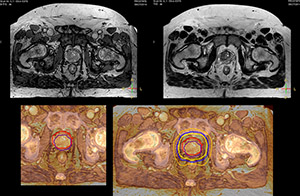

Impressive clinical benefits for prostate

“The biggest problem for CT-based planning, especially in prostate, is you can’t see the cancer very well,” says Dr. Stevens. “On CT it can be quite challenging to see the edge of the prostate especially at the apex. When the edge of the prostate can’t be delineated well on CT, radiation oncologists will increase their margins a little bit so they don’t miss it, but that can also increase toxicity.”

“Using MR, the prostate is well delineated. We quickly see the edges of cancerous tumors like in prostate cancer, and as normal structures can be defined, we can optimize the treatment plan to protect these organs and their normal function. This can potentially improve the outcome. And it improves workflow as well. We can contour more quickly, confident that the tumor is going to be in the field.”

“When a patient registers, first CT simulation and MR simulation are done, followed by CT-MR registration on Pinnacle3. Then the target and normal organ delineation is performed on MR images. Meanwhile we create a reference CT image for online treatment and localization correction. During the treatment phase we can perform additional MRI scans to visualize the anatomy changes and create an adaptive plan. This plan basically adapts the treatment plan to the changes.”